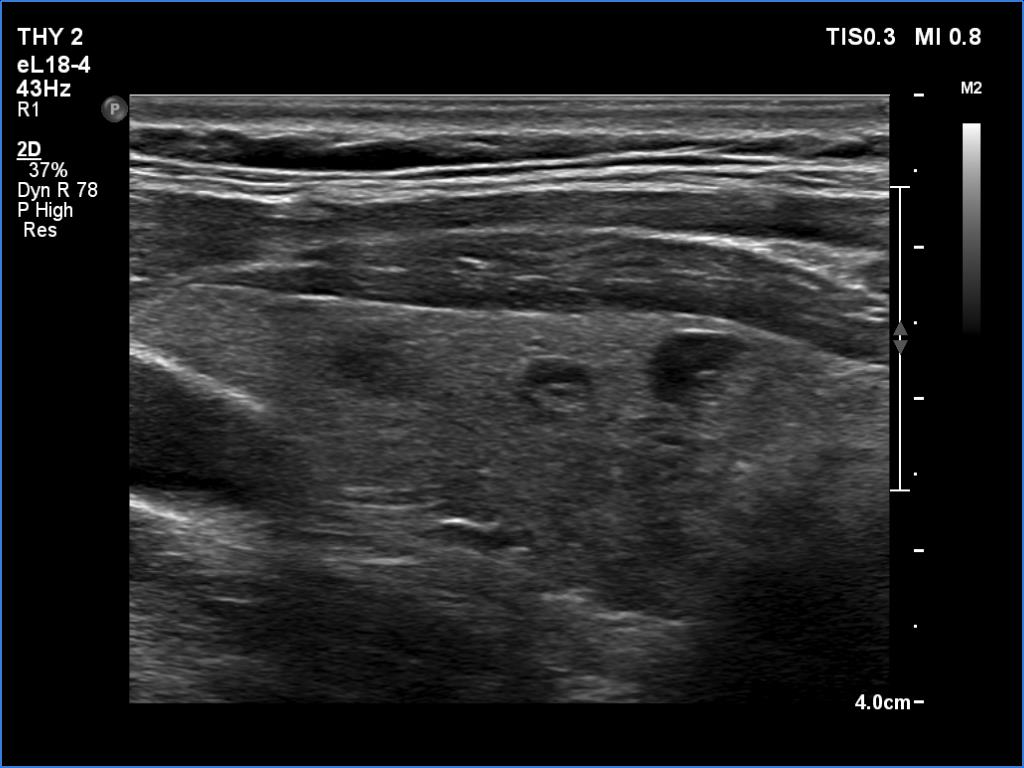

Ultrasonography. The thyroid was echonormal and had several small cystic lesions without any clinical or oncological importance. According to the palpable mass, a moderately hypoechoic lesion was detected several centimeters under the thyroid in the middle of the neck. The lesion was within the muscle tissue. It was homogeneous and presented no vascularity.